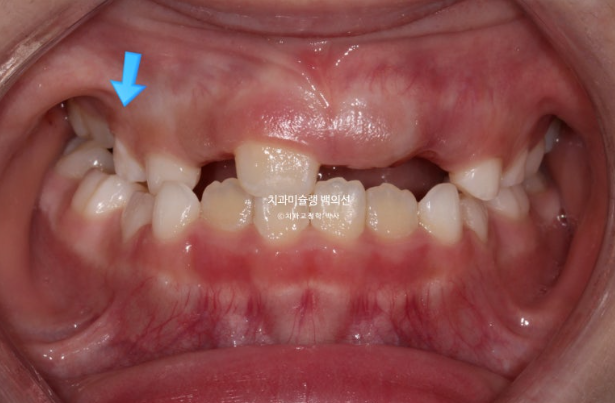

하지만 여전히 어금니 반대교합이 남아있습니다.

유치 송곳니도 여전히 거꾸로 물려 교합간섭이 남아있습니다.

어금니 반대교합은 상악 악궁이 좁아서 생기는 문제입니다.

즉 악궁확장이 필요하고 인비절라인 퍼스트로 악궁확장을 동반하여 MA (mandible advance, 하악전진기능) 기능을 이용한 비대칭 치료가 필요합니다.

드디어 앞니 4개가 나왔으며 반대교합 치료 결과는 잘 유지되고 있습니다.